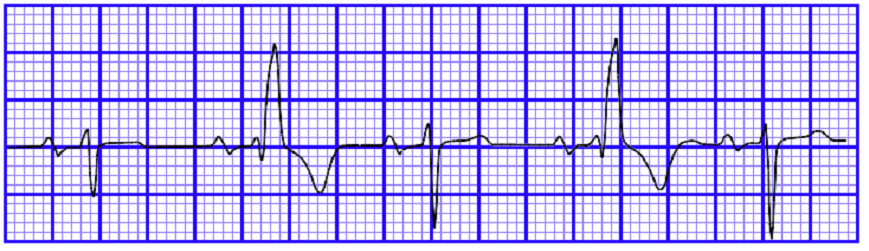

2、宽大畸形

QRS波群的宽大畸形主要是指该波群时间超过0.12s,临床上常见于室性心律,其次是室性逸搏、室内差异传导,举例聊聊三者:

室性早搏:室性早搏关键在一个“早”字,提前激动的,宽大畸形的QRS波群就是室性早搏,因为提前激动,所以叫早搏,要记住“早”这个字,室性早搏也就理解个百分之八九十了,剩下的在去区分单源性或多源性,单发、偶发还是频发,以及严重的R-on-T现象。

图4